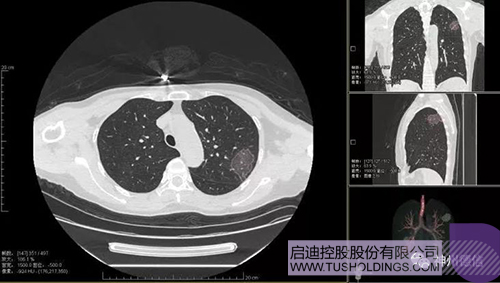

神州德信新冠肺炎檢測及智能量化分析系統(tǒng)

啟迪戰(zhàn)略投資企業(yè)神州德信作為國內(nèi)領(lǐng)先的肺部影像人工智能企業(yè),針對新型冠狀病毒肺炎開發(fā)了智能檢測及量化分析系統(tǒng),并在陜西、重慶等地定點(diǎn)醫(yī)院投入使用。該系統(tǒng)在疑似病例大規(guī)模快速篩查及精準(zhǔn)診斷方面發(fā)揮了重要作用,特別是其具有的肺炎患者臨床影像跟蹤量化隨訪功能,為快速有效阻斷疫情擴(kuò)散提供了有力武器。